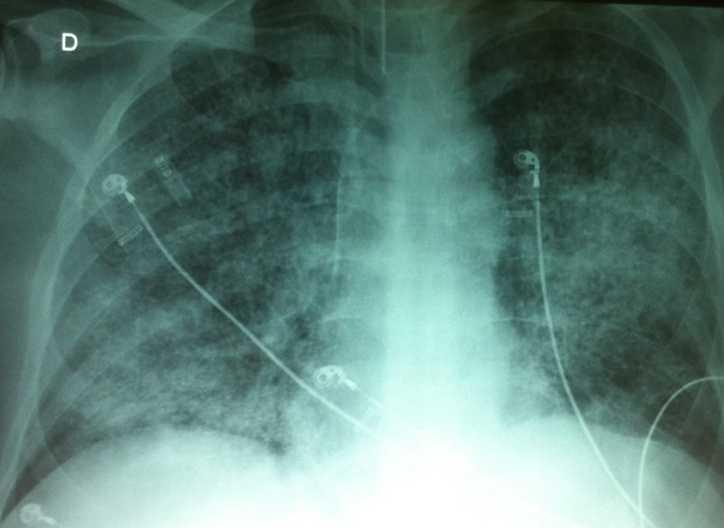

Um médico intensivista tentava otimizar os ajustes da ventilação mecânica em um paciente de 66 anos, com diagnóstico de sepse e Síndrome da Angústia Respiratória Aguda, intubado há 8h, com o Raio-X de tórax abaixo:

Raio-x de tórax em AP evidenciando opacidades intersticiais e alveolares bilaterais.